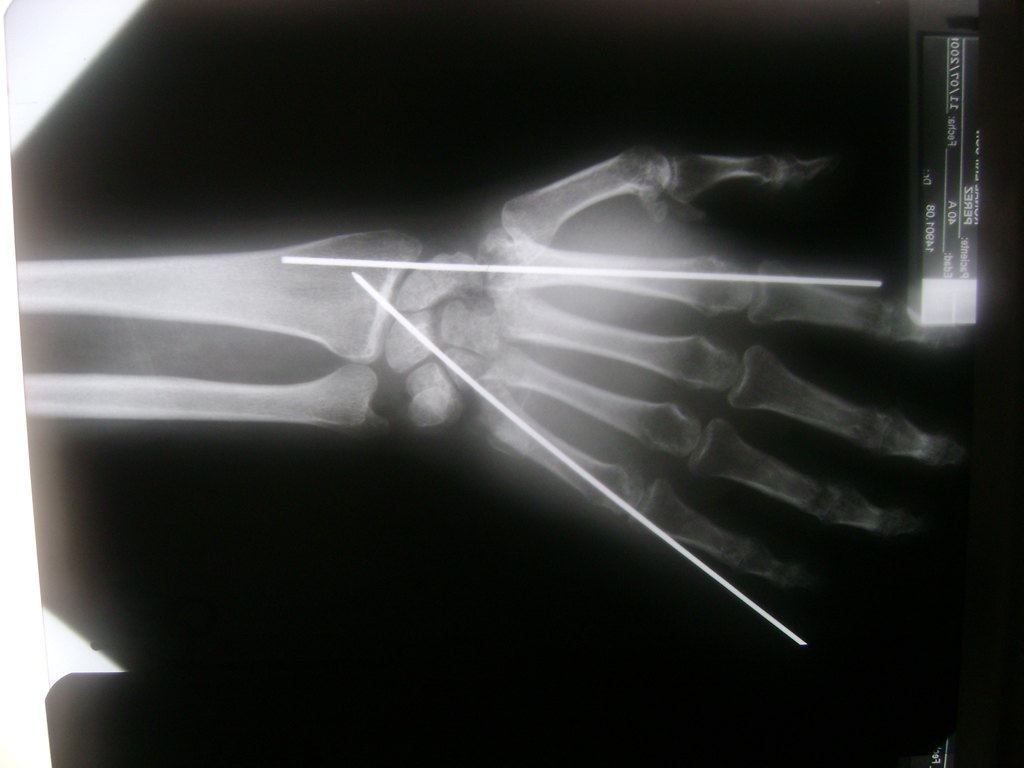

Cirugías de Hombros - Cirugías de Muñecas y Manos

Los procedimientos más comunes en cirugía de la mano son aquellos destinados a reparar traumatismos, incluyendo lesiones de tendones, nervios, vasos sanguíneos, y articulaciones; huesos fracturados; y quemaduras, cortes, y otros daños de la piel.